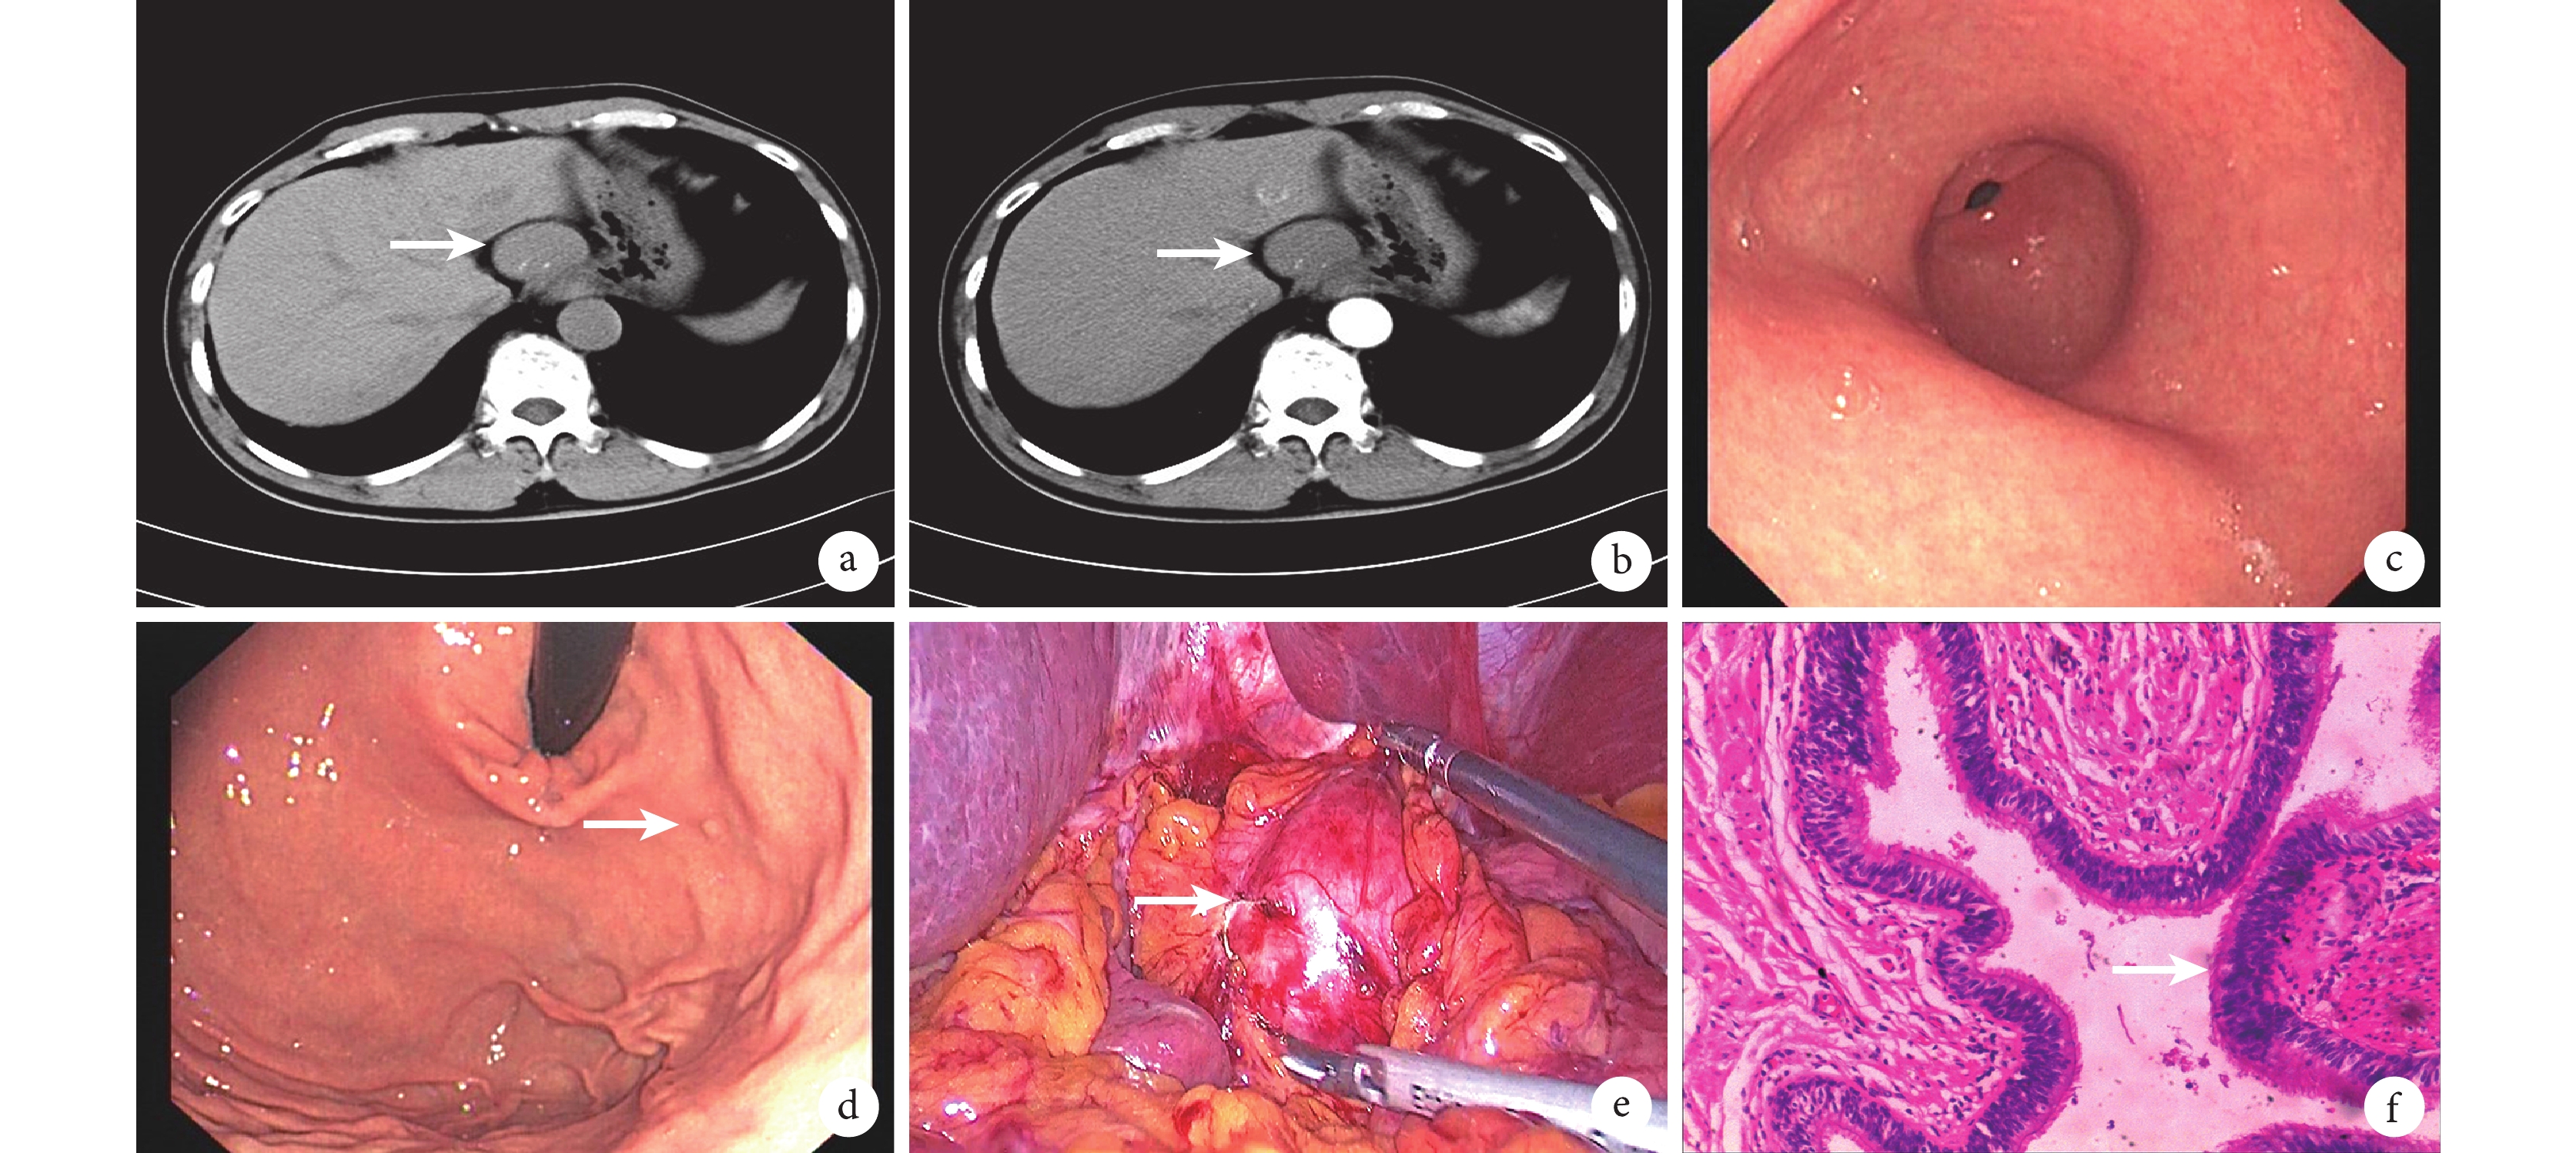

a:全腹部 CT 平掃見肝胃間隙一約 42 mm×33 mm 大的軟組織密度腫物(白箭),腫物位于肝胃間隙,與肝臟分界清楚,邊緣光滑,內見少量點狀和小結節狀鈣化灶;b:CT 增強掃描動脈期圖像見病變(白箭)無明顯強化;c 和 d:上消化道內鏡見食管腔各處形態及黏膜色澤未見異常,胃腔內除見一枚直徑約 0.2 cm 的息肉(白箭)外未見腫物或隆起性病變,形態及黏膜色澤未見異常;e:術中見腫瘤位于食管腹段,向腔外生長,呈囊性,約 4.0 cm×3.0 cm×4.0 cm 大(白箭);f:術后病理學圖像見囊壁由平滑肌組織構成,內襯假復層纖毛柱狀上皮(白箭),病理診斷為(食管腹段)支氣管源性囊腫(HE ×40)